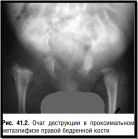

Рентгенологические признаки остеомиелита у новорожденных появляются на 7–10-е сутки от начала заболевания. При местной форме первыми рентгенологическими признаками могут быть утолщение мягких тканей и надкостницы, краевая или очаговая деструкция костной ткани (рис. 41.2).

При тяжелых формах определяются расширение суставной щели, патологический вывих, зона деструкции, занимающая более половины ширины метафиза, линия патологического перелома.